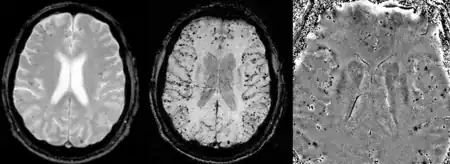

MRI showing low signal foci in cerebral amyloid angiopathy. Conventional gradient echo T2*-weighted image (left, TE=20ms), susceptibility weighted image (SWI) and SWI phase image (center and right, respectively, TE=40ms) at 1.5 Tesla.[26]

CAA can only be definitively diagnosed by a post-mortem autopsy.[27] Biopsies can play a role in diagnosing probable cases.[28] When no tissue is available for biopsy, the Boston Criteria are used to determine probable CAA cases from MRI or CT scan data. The Boston Criteria require evidence of multiple lobar or cortical hemorrhages to label a patient as probably having CAA.[27] Susceptibility weighted imaging has been proposed as a tool for identifying CAA-related microhemorrhages.[29]

MRI sequence of gradient echo and susceptibility weighted imaging (SWI) are useful in detecting microbleeds and deposition of iron on the brain cortex (cortical superficial siderosis).[19] Other MRI indicators of CAA include white matter hyperintensities and cortical thinning.[30]